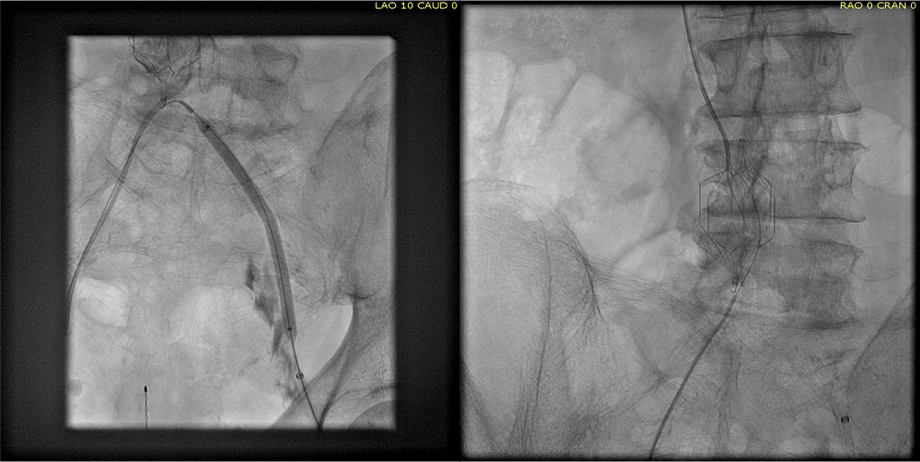

Examination revealed a fit and trim man in his 70’s in no apparent distress. He had bilateral leg edema that was moderate with small superficial and tender ulcers of the right posterior distal calf. Pulses were normal. He was taken to our hybrid suite and venography from femoral vein access in the proximal thigh in the supine position revealed his right and left iliac venous systems to be occluded (below figures).

right initial venogram

Right injection from femoral sheath showing occluded iliac vein with collaterals

left initial venogram.png

Left injection

Wire access into the iliac systems was performed with Glidewire and Glidecatheter periodic venography to confirm that I had not exited the vein. Unlike the arterial system, extravasation from being extravenous does not have the consequence of bleeding, hematoma development, and pseudoaneurysm formation because of the low pressure, but it can be a long procedure and uncomfortable as well so these are done under general anesthesia.

intervention fig 1.png

Advancing wire and sheath into iliac vein, crossing filter resulted in extravasation of contrast

Once position confirmed to be in the iliac vein, the vein was dilated to allow for greater ease of movement. In the case of the uncrossable filter, I switched to access from above via a right internal jugular vein access.

intervention fig 2.png

Dilating vein (left) for greater mobility, and crossing from above (R. IJV access)

Once the wire crossed into the iliac vein from above, it was captured and brought out. While ballooning by itself is inadequate for revascularization, it greatly eases wire capture and on the right, it was done simply by driving the wire from above into the sheath. Wire capture wins access across the iliocaval and IVC filter occlusion from below.

intervention fig 3.png

Wire passage across IVC filter into right and left systems